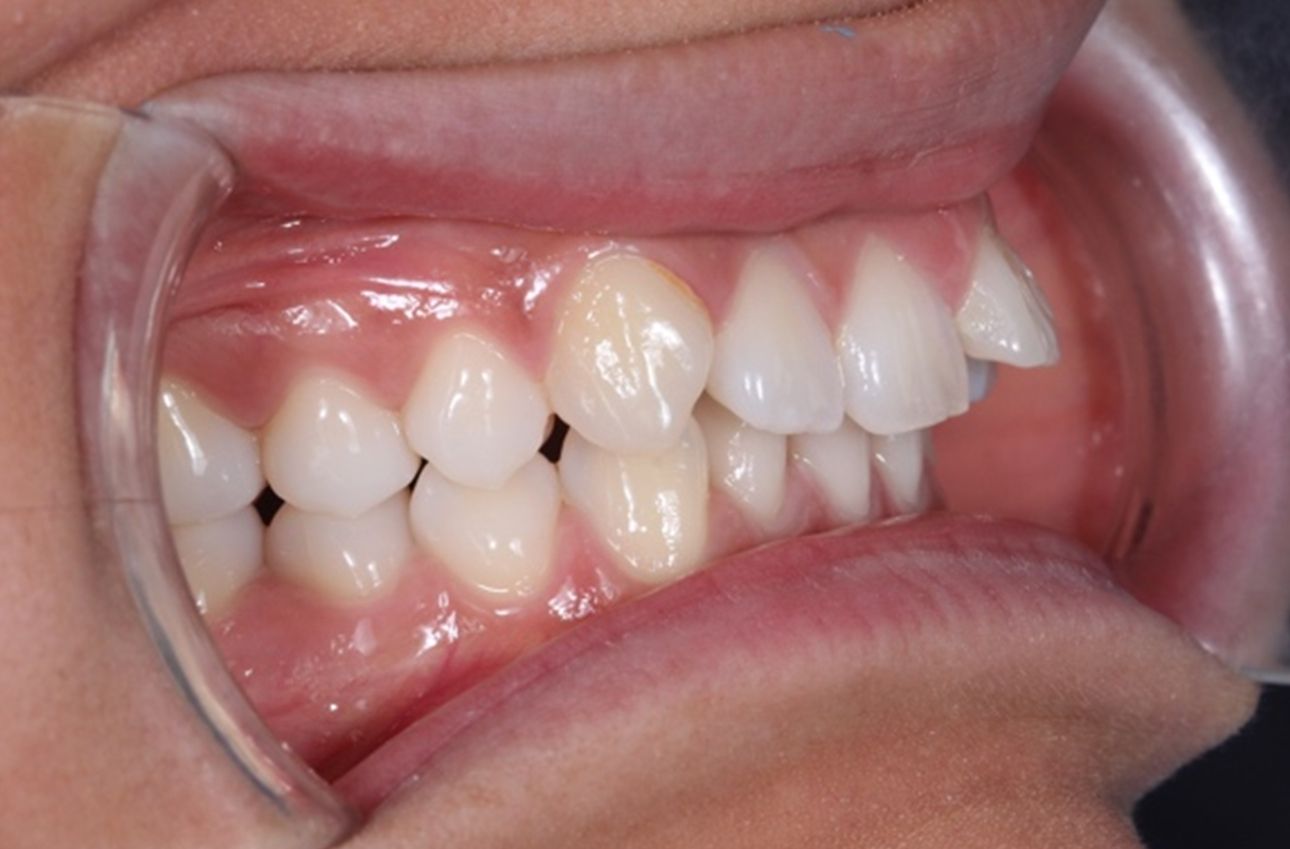

A continuación, mostramos el caso de una paciente adulta con clase II ósea y dentaria.

Con Ortodoncia Invisible, y gracias a la cooperación de la paciente, conseguimos este resultado y, lo más importante de todo, que la paciente sonría sin complejos.